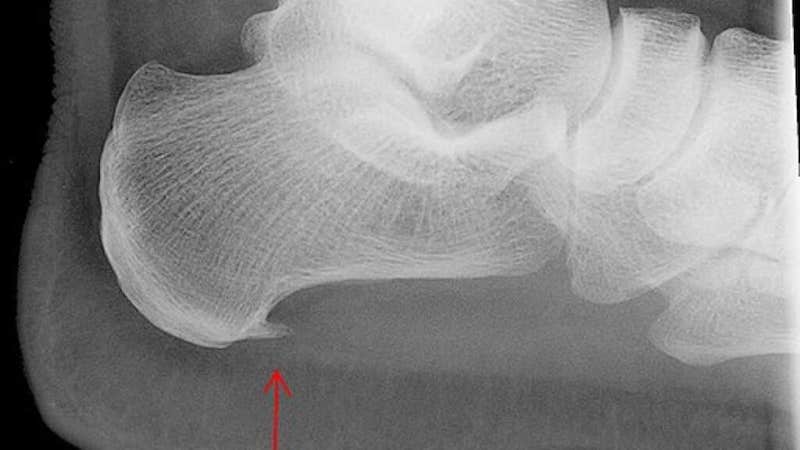

Imate petni trn - šta savetuje vaš fizijatar?

Imate petni trn? Pročitajte savet fizijatra o tome da li treba i kako lečiti petni trn. Ceo tekst pročitatje ovde.